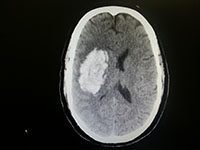

My name is Rohan Mullin. I suffered a stroke back in April 2013 and I have attached a photo that shows the size of my bleed. I lost the use of my left side which meant the use of my arm and ability to walk. I have been using Neuroaid since May 2nd and I’m already seeing improvement. In my affected side which I still have to put in more work to improve but I look forward to achieving my goals. The team at Sunshine and Footscray Hospital are keen to see how things go. Even my local GP is looking to prescribe Neuroaid to his 92 year old father whom has just suffered a stroke back in India.

rohanmullinbrainmriscan